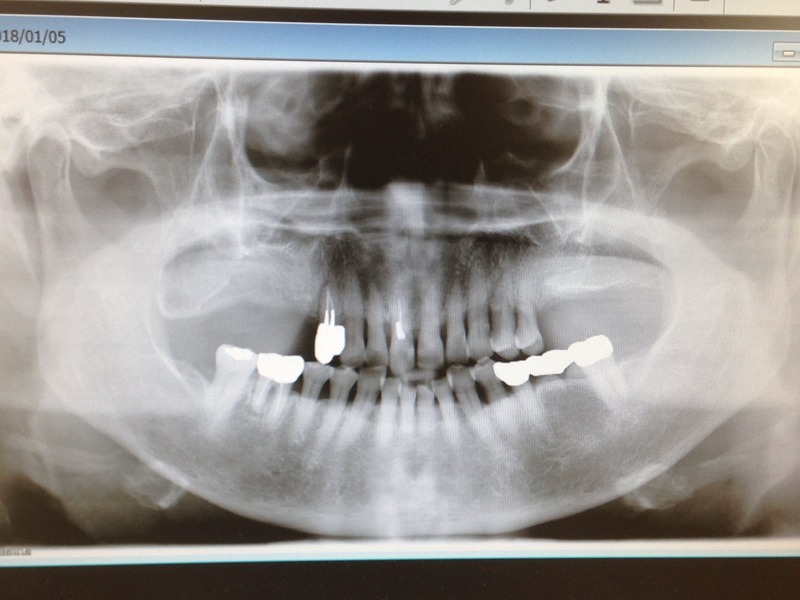

上の写真の左は、従来の(二次元の)パノラマ写真です。右は、CT撮影された三次元的な写真です。

どう考えても二次元のパノラマ写真より、CT撮影された三次元的な写真の方が情報量が多いので、正確な診断、状況把握ができます。